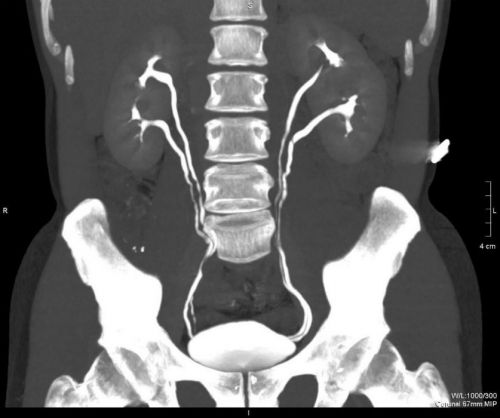

Двойная почка часто обнаруживается у взрослых людей и детей при ультразвуковом сканировании. Врач-сонолог замечает наличие пары независимых друг от друга систем чашечек и лоханок в пределах одного органа. На удвоение также указывает размер, превышающий норму, наличие перемычки.

На УЗИ не всегда достаточно четко визуализируется полное удвоение, а также изменение строения мочеточника. Для их выявления проводят урографию – рентген, незадолго до которого внутривенно вводят контрастное вещество.

Во время УЗИ специалист может догадаться о раздвоении почек только в том случае, если он распознает две самостоятельные чашечно-лоханочные системы. Чтобы подтвердить предположение, врачи отправляют пациента на цистоскопию или на восходящую урографию. В ходе цистоскопии специалист способен рассмотреть устье мочеточников.

При удвоении почки их будет два. Если удвоение произошло с правой почкой, два мочеточника будут входить в мочевой пузырь. Восходящая урография основывается на введении в организм красящего пигмента, который отражается на рентгене. На снимке врач может полностью разглядеть чашечно-лоханочную систему.

Диагностика аномалии осуществляется преимущественно во время процедуры УЗИ.

При полном раздвоении специалист видит две самостоятельно функционирующие чашечно-лоханочные системы.

Для подтверждения нарушений в строении органа пациента направляют на цистоскопию (изучение поверхности мочевого пузыря изнутри эндоскопом) или экскреторную урографию (рентгенологическое исследование с введением контрастного вещества).

Урограмма в состоянии определить структуру мочевыводящих путей.